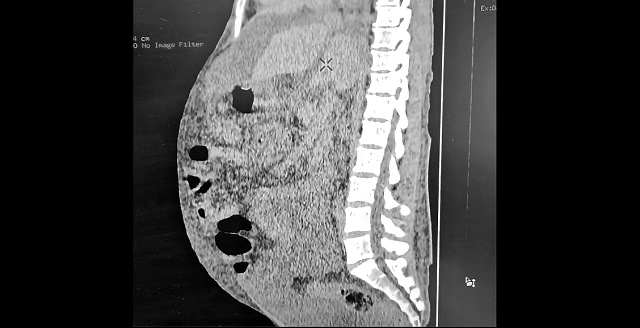

32-летний житель Набережных Челнов заработал себе цирроз печени, злоупотребляя спиртными напитками. Вследствие чего в его животе скопилось 10 литров свободной жидкости, передает пресс-служба Горздрава автограда.

По словам завотделением лучевой диагностики горбольницы №5 Рузаны Миннехановой, практически все органы пациента необратимо повреждены, особенно печень. Состояние пациента удалось стабилизировать, но о полном выздоровлении речь не идет.